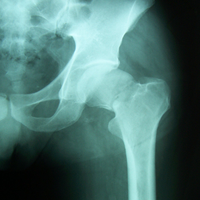

Case:11 Fracture Intracapsular Neck Femur

80 years old female patient treated with bipolar prosthesis.

Pre-Op

Post-op